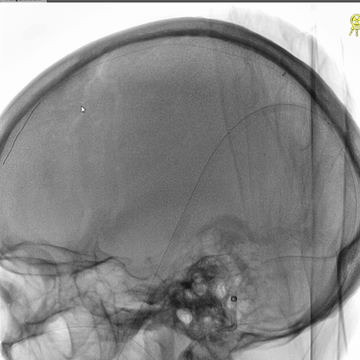

右侧颈动脉造影(正侧位):上矢状窦和直窦未见显影;右侧横窦和乙状窦少许显影。

左侧颈动脉造影(正侧位):上矢状窦前部少许显影,直窦未见显影,左侧横窦和乙状窦显影纤细。